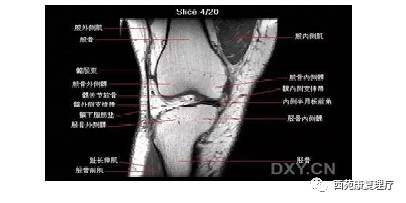

股四头肌是引起老年人膝骨关节炎最主要的肌肉,股内、外侧肌和股直肌、股中间肌共同构成了股四头肌,内外侧肌共同维持着髌骨在膝关节上的位置。如果股内、外侧肌出现损伤,则会导致膝关节内外侧疼痛,髌骨移位,形成膝内翻和膝外翻;股直肌是双关节肌,跨过髋关节和膝关节,容易引起大腿前侧的疼痛,也会导致人下蹲受限,有时病人也会感觉大腿后侧的牵拉感。股四头肌在临床上是一块比较易受损的肌肉,很多膝关节疼痛的病人在处理完股四头肌后会有明显的改善。